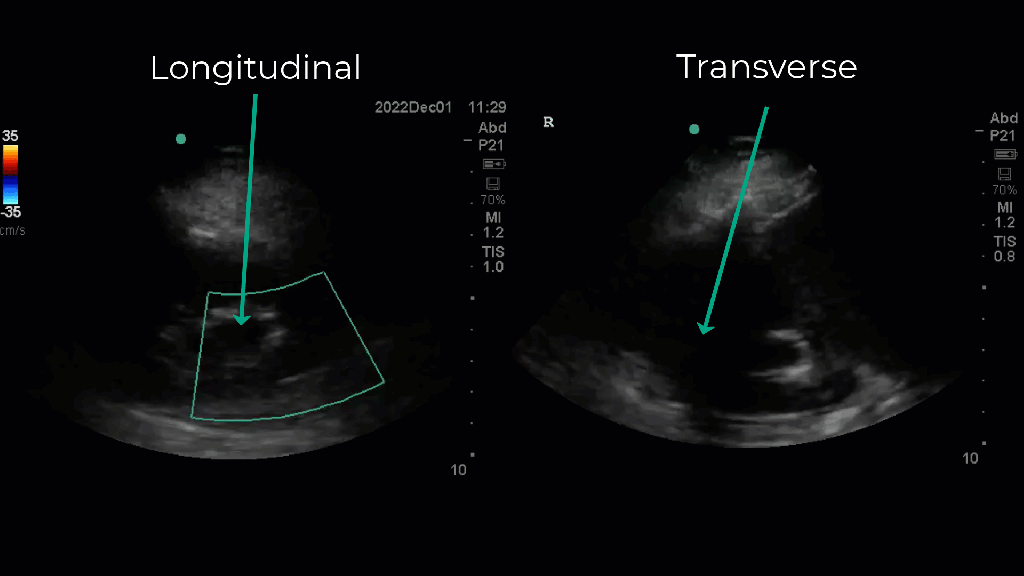

Extra-renal pelvis: In some normal individuals the renal pelvis exists OUTSIDE of the renal sinus which makes it much more distensible. Notice in this patient on the left the massive central “dilation” but without any calyceal dilation (left clip) which when viewed in transverse is seen to be outside of the renal sinus. This is precisely the reason which looking at the kidney in two planes is so important.